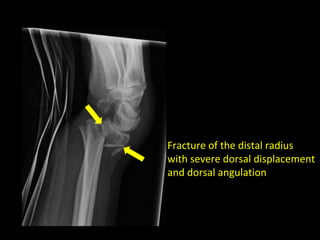

How to describe fractures

• Is there displacement?

• e.g. “there is lateral displacement of the distal fracture

component”

• Is there angulation?

• e.g. “there is medial angulation of the distal fracture

• As you would expect, the more displaced and/or angulated a

fracture is, the more likely it will require surgical intervention

Fracture of the distal radius

with severe dorsal displacement

and dorsal angulation